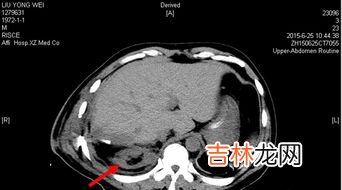

文章插图